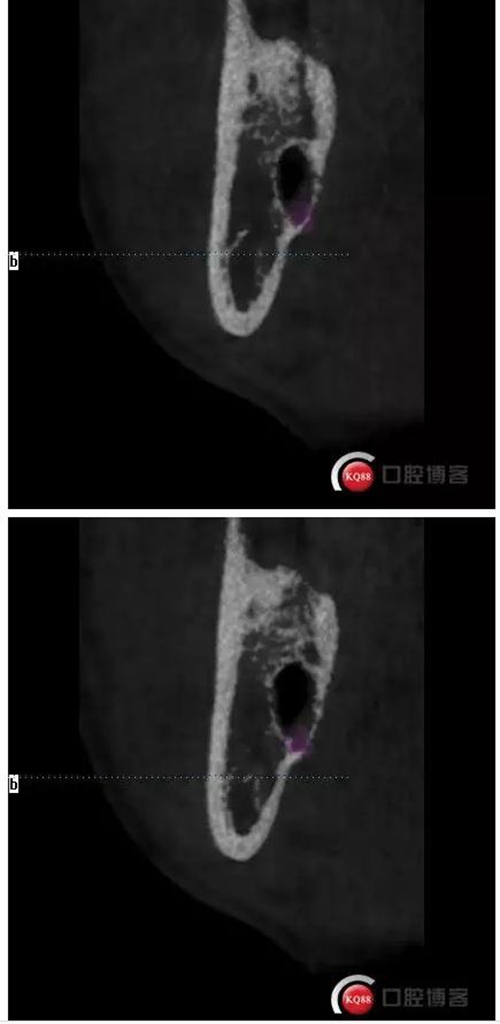

下面拔除后的片子,可以清楚的看到,牙根穿破神經(jīng)管。

拔牙前后對比一下,(拔除前)

1500633362_825152.jpg拔除后。 可以看到神經(jīng)管皮質(zhì)骨的不連續(xù)。